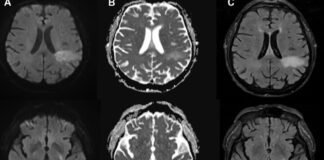

JC virus

You’re likely already infected with a brain-eating virus you’ve never heard...